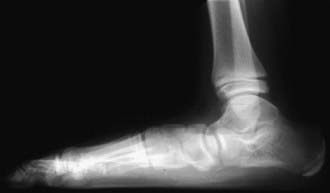

Radiographic Evaluation

Routine radiographs of asymptomatic flexible flatfeet are usually not indicated. Weight-bearing radiographs (AP and lateral) are required to assess the deformity. On the AP radiograph, there is widening of the angle between the longitudinal axis of the talus and the calcaneus, indicating excessive heel valgus. The lateral view shows distortion of the normal straight-line relationship between the long axis of the talus and the 1st metatarsal, with a sag either of the talonavicular or naviculocuneiform joint, resulting in flattening of the normal medial longitudinal arch (Fig. 666-4).

image

Figure 666-4 Lateral weight-bearing radiograph demonstrating features of flatfoot.